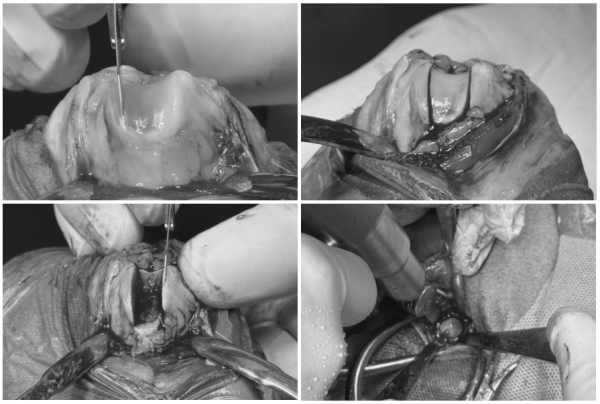

마취 전 정밀 검사 후

고양이 슬개골 탈구 교정 수술

FHNO(Femoral Head and Neck Ostectomy)수술

을 동시에 진행하기로 계획하였습니다.

FHNO수술이란?

FHNO수술은 대퇴골두와 경부를 제거하여

고관절 통증의 근본적인 원인을 제거하는 수술입니다.

수술 후에는 주변 근육과 연부 조직이

새로운 가성 관절(pseudo joint)을 형성하게 되며,

이를 통해 통증 없이 보행이 가능하도록 유도합니다.

루미는 양측 고관절과 슬개골이 다 문제가 되는 상태여서 수술을 한꺼번에 진행할 수 없었고,

촉진상 고양이 슬개골탈구 단계가 조금 더 높았던 좌측을 먼저 수술한 뒤

2-3개월 회복과정을 거친 후 우측 다리를 수술하기로 계획하였습니다.

좌측 슬개골 탈구 교정술과 대퇴골두절단술을 같이 진행하였습니다.